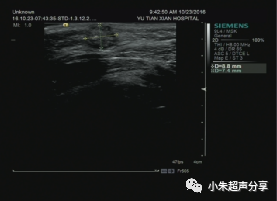

病例3   女 ,12岁,右侧面部毛母质瘤

其内可见斑块状钙化